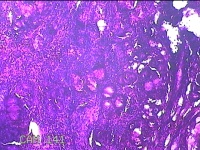

左侧鼻腔病变组织

性别

男

年龄

28岁

临床诊断

1.慢性鼻窦炎 2.鼻中隔偏曲 3.变应性鼻炎

一般病史

反复鼻塞10余年,加重伴脓涕3天。

标本名称

大体所见

灰白暗红色组织0.8x0.3x0.2cm一块,表面糜烂,内有少许骨质。